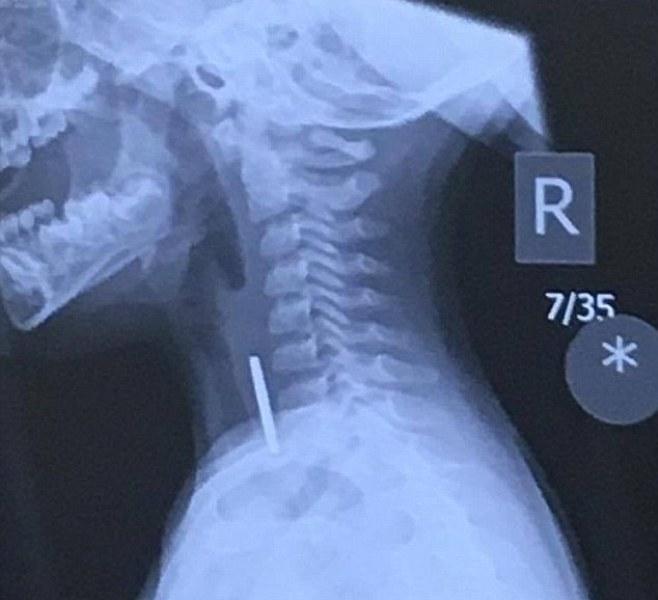

Η μητέρα του πανικόβλητη το πήγε στο νοσοκομείο, όπου οι γιατροί διαπίστωσαν ότι ένα κέρμα έφραζε το λαιμό του, κόβοντάς του την αναπνοή.

Το παιδάκι οδηγήθηκε εσπευσμένα στο χειρουργίο, προκειμένου το κέρμα να αφαιρεθεί από το λαιμό του, ενώ οι γιατροί τόνισαν ότι αν το νόμισμα δεν είχε σφηνωθεί οριζόντια, αλλά κάθετα, τότε το παιδί θα είχε πεθάνει από ασφυξία.